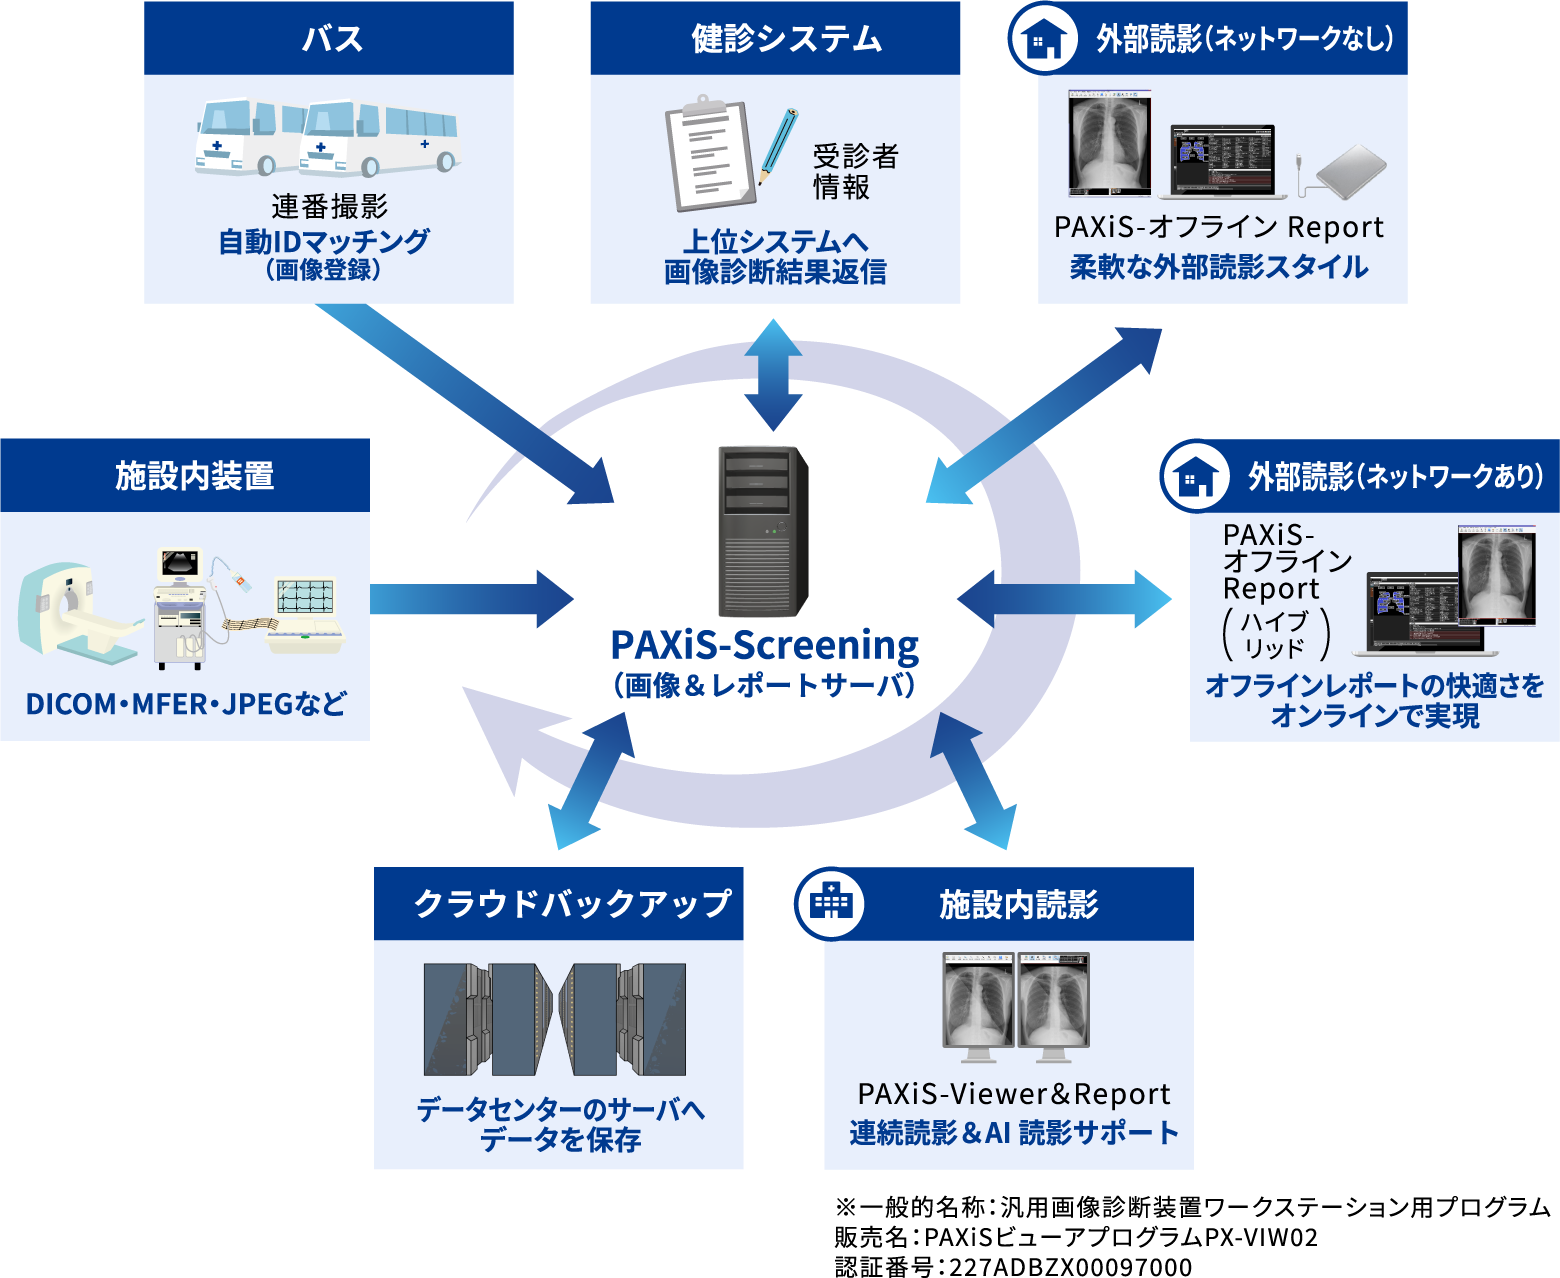

PAXiSパクシス-Screeningスクリーニング は、

健診に特化したPACS&レポート機能はもちろん、

読影進捗管理、マッチング、

MWM、遠隔読影機能など

読影に関わる全ての機能をオールインワンで搭載。

画像登録から結果確定までの健診読影業務を

トータルサポート!

外部読影も簡単にシステム化したい!

- セキュリティ機能付きのメディアを使い、外部でもレポート入力可能

- ネットワークも事前のソフトウェアインストールも不要!手軽に読影開始

- メディアからビューア&レポートが起動し、自宅や勤務先のPCで所見入力

- ネットワーク環境下では、オンラインでのデータ授受も可能

- 連番撮影のマッチングを自動化し、作業時間を大幅削減

クラウドで管理したい!

- 「3省2ガイドライン」に準拠

- BCP対策としてデータのバックアップ・長期保管に対応

- 自社データセンターにて安心安全のサービス提供 ※国際規格認証を取得